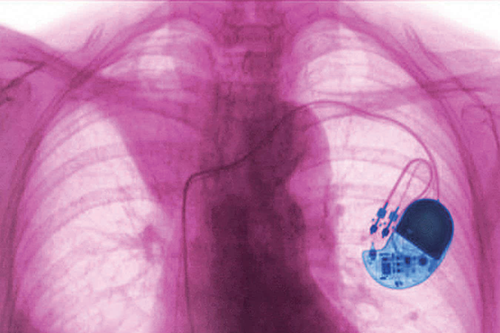

但好景不长。毕竟,目前用于修复身体损伤或应对功能衰退的植入设备都存在一个问题:不能永久耐用。无论是全球数量约为300万个的心脏起搏器,还是其他各类植入设备,都是如此。人工硬件与柔性的人体组织难以兼容,免疫系统会攻击这些外来物。

现代植入设备正是嵌入了这些电回路中。心脏起搏器维持心跳节律,脑深部电刺激装置释放电脉冲以改善帕金森病的症状,人工耳蜗通过刺激内耳神经使人恢复听力。目前,科研人员还在研发可助人恢复视力的视网膜植入设备。

不过,人体对不同植入设备的耐受度差异极大:心脏起搏器通常耐受性较好,电池可使用15年之久,但脑深部电刺激装置一般只能用3至5年。而伯克哈特的实验性大脑植入设备,曾创造了7年使用寿命的记录。

心脏起搏器通过向心肌发送弱电脉冲来治疗心律失常